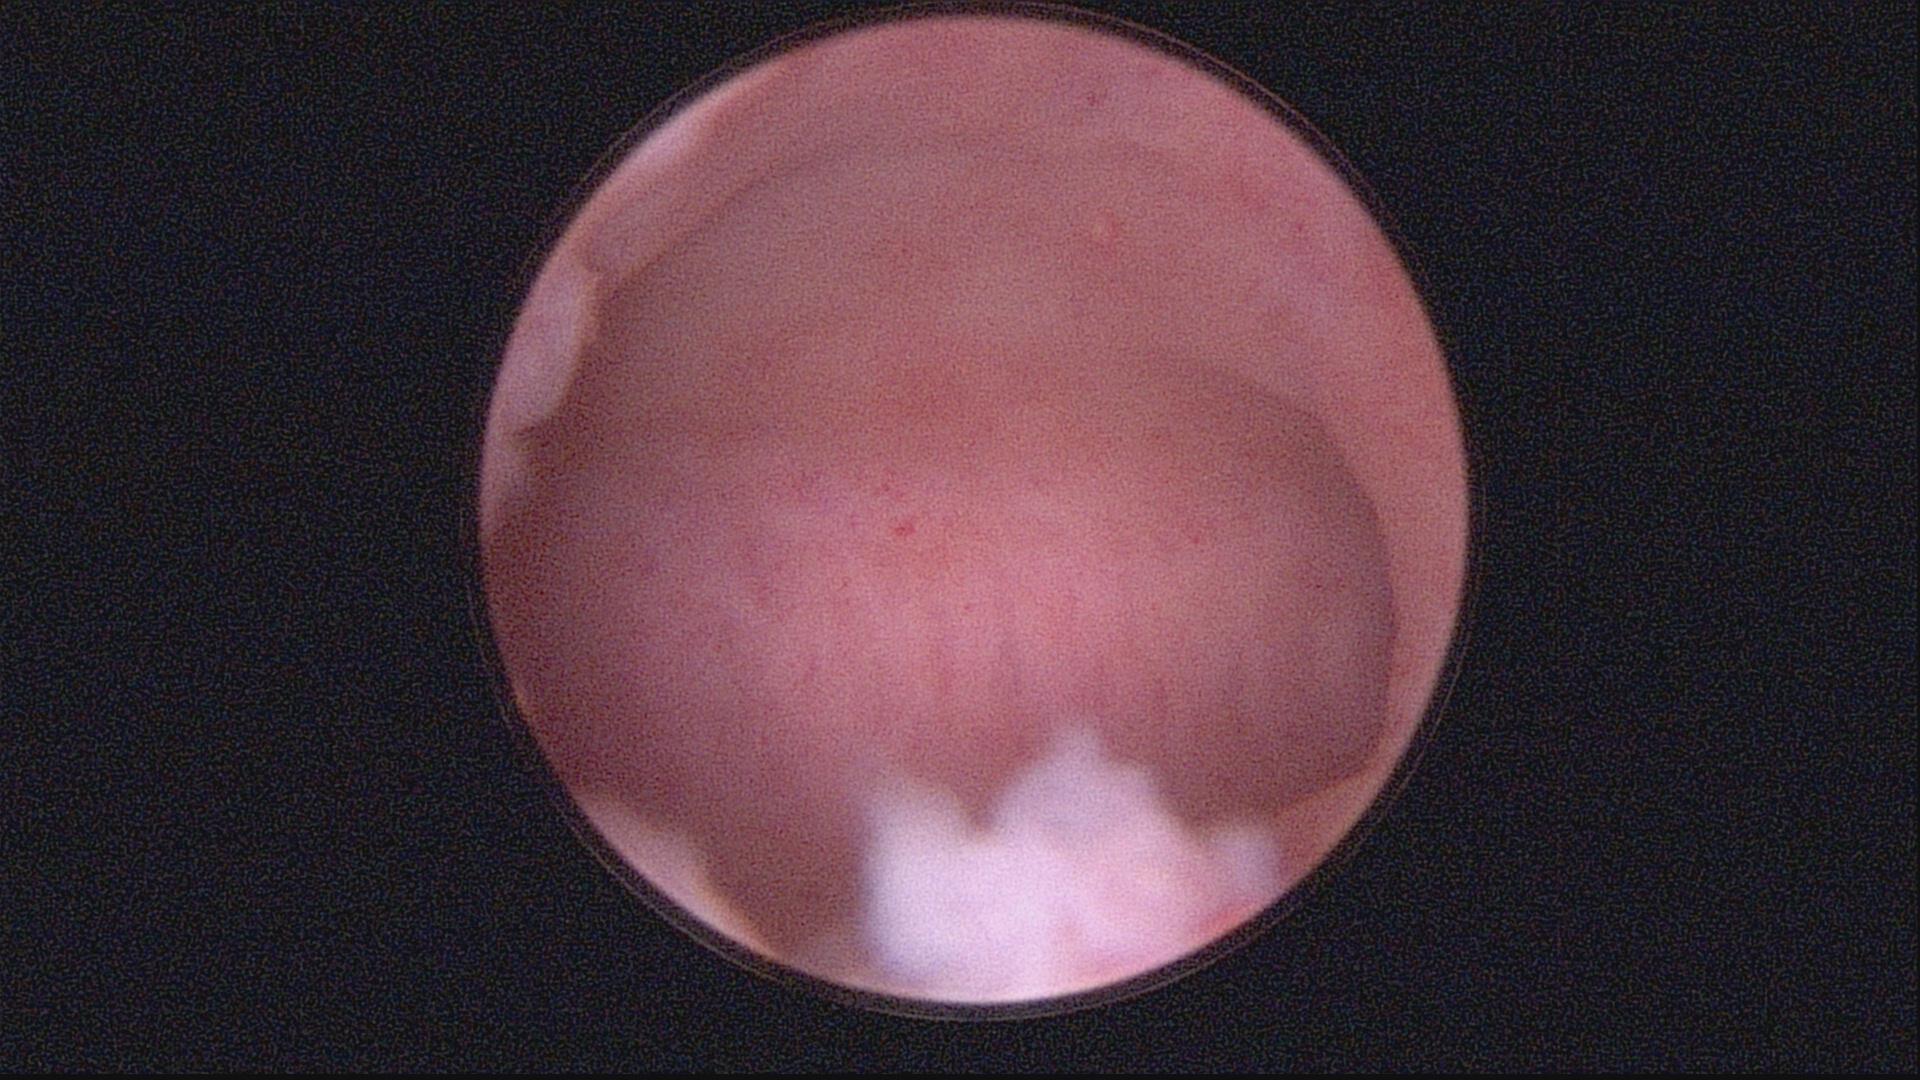

图三:宫形环支撑

注:宫腔粘连手术是关键,术后还要综合治疗,宫腔放置球囊和宫形环支撑宫腔。配合防黏连的凝胶以及雌激素药物让子宫内膜更好的生长。